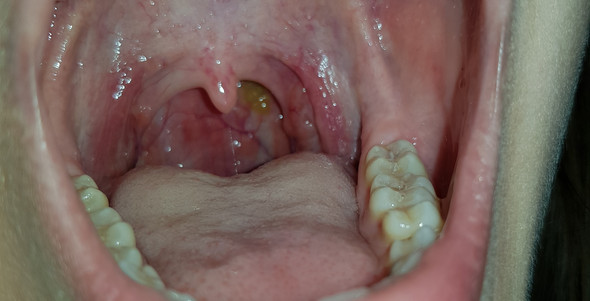

Was Ist Der Gelbliche Schleim Im Rachen Gesundheit Und Medizin Rachenentzundung

Erkältungssymptome die den Symptomen einer Nasennebenhöhlenentzündung ähnlich sind. Erst bei SchluckbeschwerdenSchmerzen und eitrigen Belägen auf den Schleimhäuten sollte sicherheitshalber ein Arzt aufgesucht werden rät Dr. Halsschmerzen und grüner Auswurf.